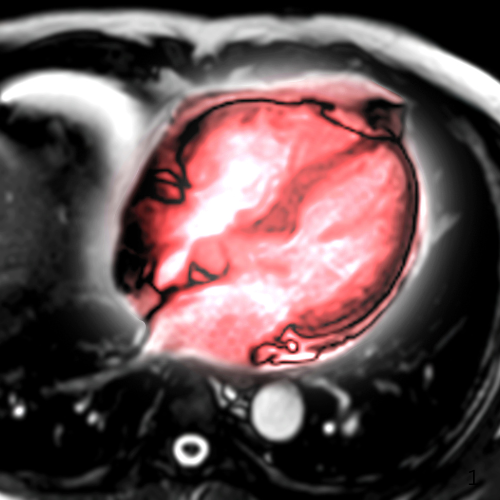

If there’s one thing we can all agree on, it’s that cardiac care is becoming more critical than ever. Heart disease rates are climbing, people are living longer, and the demand for early diagnosis and accurate imaging has never been higher. As Diagnostic Imaging Centers, you’re on the front lines of this growing need. The good news? Advancements in MRI and CT scanners are making cardiac imaging faster, clearer, and more efficient. But keeping up with these changes can feel like running on a treadmill set to full speed. Let’s talk about how you can meet this demand, stay ahead...